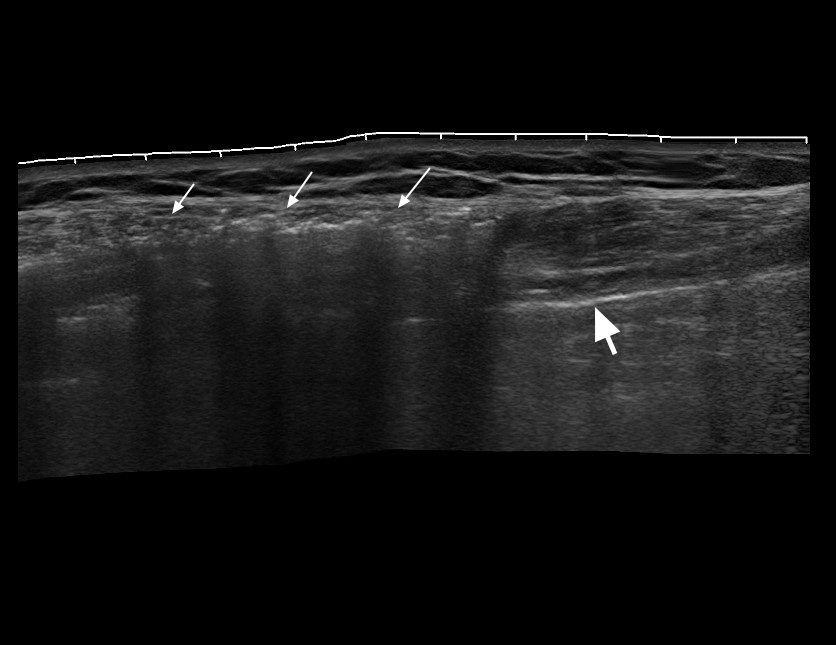

Пожилой человек, упал с лестницы в саду. Жалобы на сильные боли в грудной клетке и пояснице справа. Одышки нет.

Пальпаторно справа - подкожная крепитация.

Ультразвуковое панорамное изображение и видео подкожной эмфмземы при травме грудной клетки. В подкожно-жировой клетчатке определяется воздух (стрелки). Линия плевры находится глубже воздуха (толстая стрелка). Пальпаторно в зоне скопления воздуха определяется крепитация. Позади воздуха определяются Е-линии. Обратите внимание на подвижность линии легкого и неподвижность "залипшего" в верхней точке грудной клетки воздуха.

Справа во IIм межреберье в плевральной полости определяется небольшое количество свободного воздуха.

Слева воздух не определяется.